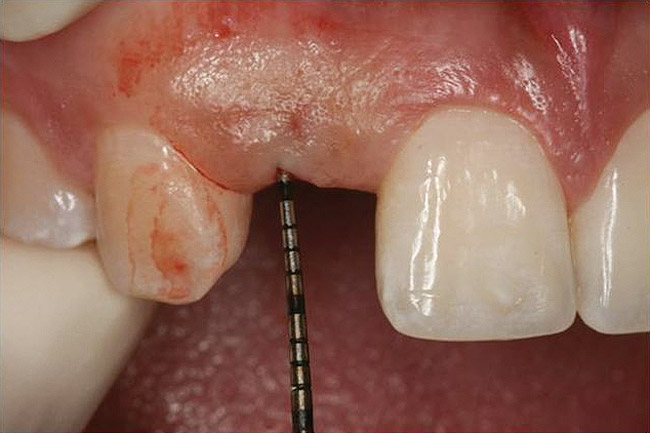

Figure 10 Clinical examination of the bound edentulous space: Measurement of the distal (Fig 10) and mesial (Fig 11) interproximal tissue height using a periodontal probe supplements data obtained from the periapical radiograph. Estimation of the buccal t

Figure 10

Figure 11 Clinical examination of the bound edentulous space: Measurement of the distal (Fig 10) and mesial (Fig 11) interproximal tissue height using a periodontal probe supplements data obtained from the periapical radiograph. Estimation of the buccal t

Figure 11

Figure 12 Clinical examination of the bound edentulous space: Measurement of the distal (Fig 10) and mesial (Fig 11) interproximal tissue height using a periodontal probe supplements data obtained from the periapical radiograph. Estimation of the buccal t

Figure 12